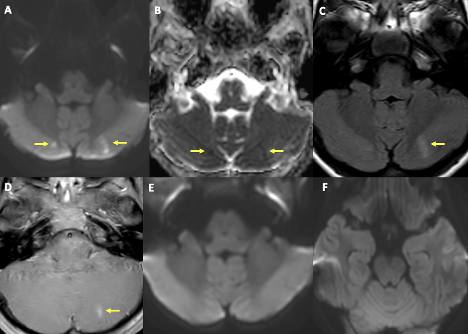

One week into hospitalization, the patient had episodes of auditory and visual hallucinations, followed by staring off to the right side. An electroencephalogram revealed evidence of a lower seizure threshold within the left hemisphere and background slowing (more in the left hemisphere than the right). She was started on levetiracetam 15 mg/kg twice daily and given midazolam 0.05 mg/kg as needed. A computed tomography of the head and brain was within normal limits, but the MRI revealed findings in the supratentorial cerebral parenchyma in the left medial temporal lobe that likely represented postictal changes, in addition to a small acute ischemia/infarction in the right cerebral hemisphere and small subacute ischemia/infarction in the left cerebral hemisphere (Figures 2 and 3).

Figure 2. MRI of the brain showed foci of diffusion restriction in bilateral paramedian cerebellar hemispheres in relatively symmetrical distribution (yellow arrows in A, B). There is fluid-attenuated inversion recovery signal abnormality and contrast enhancement corresponding to lesion in the left cerebellar hemisphere (yellow arrows in C, D). MRI is at the same level from 8 days ago (E, F). The overall imaging pattern is suggestive of acute infarct in the right cerebellar hemisphere and subacute infarct in the left cerebellar hemisphere.